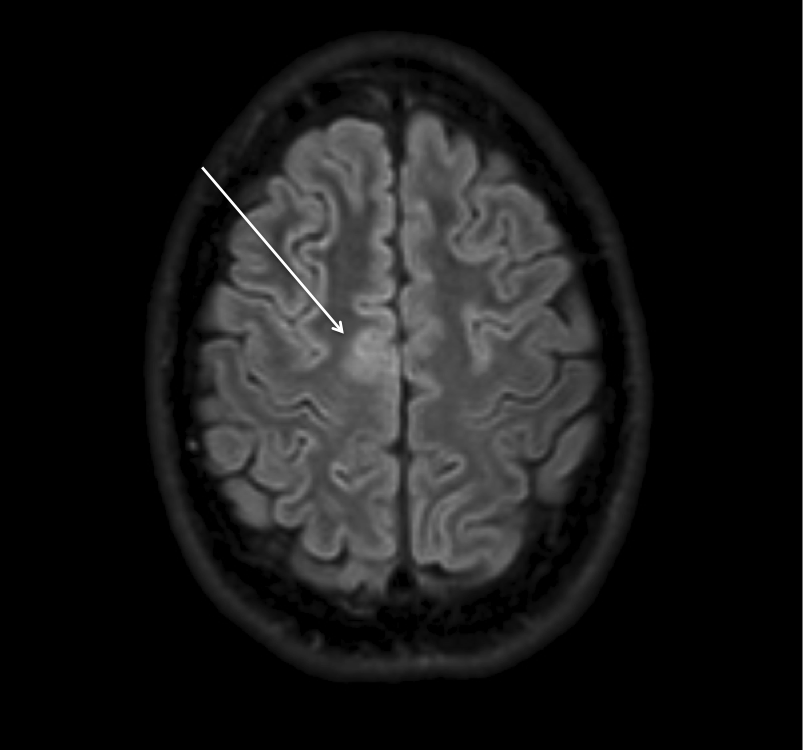

There is a localized area of cortical thickening, with blurring of the grey-white matter junction and increased signal in the underlying white matter on FLAIR imaging, seen in the left frontal lobe

FCD II